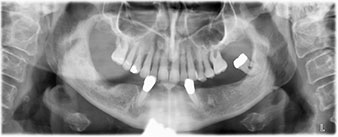

La paciente de 64 años se presentó con una dentición residual compuesta por las piezas dentales 38, 33 y 43 en el maxilar inferior y con una prótesis temporal fijada con ganchos en el maxilar inferior (figs. 1 y 2).

dentición residual

Fig. 1

Fig. 2

El tratamiento periodóntico necesario y la extracción de las piezas en el maxilar superior debía realizarse en un momento posterior, ya que la paciente es profesora y, en el momento de la consulta, estaba ocupada con los exámenes para las pruebas de acceso a la universidad. La paciente no podía comer ni hablar adecuadamente, ya que la prótesis temporal se rompía con mucha frecuencia y con una carga mínima.

Tras explicarle las distintas opciones de tratamiento, la paciente se decidió por la extracción de la dentición residual en el maxilar inferior, la implantación inmediata y el tratamiento con el método Fast & Fixed (bredent medical), con el que la prótesis dental fijada provisionalmente se atornilla sobre cuatro implantes en el mismo día de la intervención. El objetivo era operar a la paciente el viernes para que el lunes pudiera tomar parte en los exámenes orales para la prueba de acceso a la universidad.